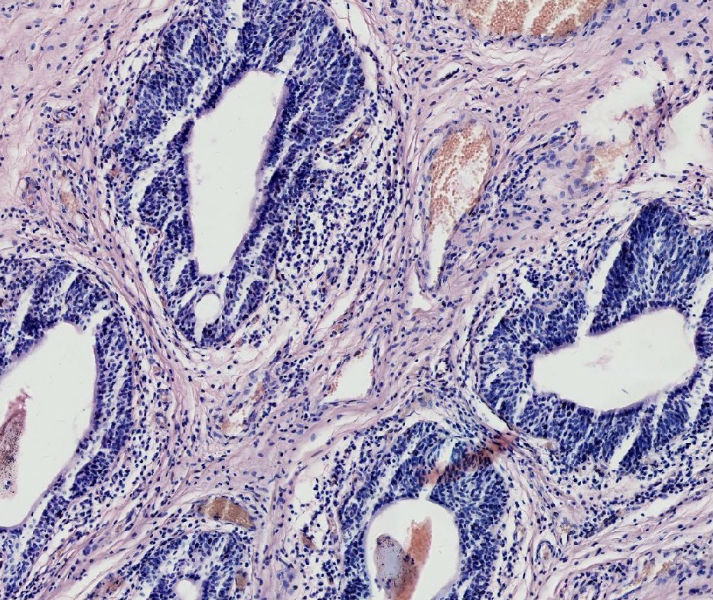

女57岁发现尿道外口息肉二周

上皮下间质中有淋巴细胞浸润,移行上皮巢团中央有柱状上皮围成的腺样腔隙。诊断:腺囊型尿道炎。

腺囊性尿道炎

尿道肉阜